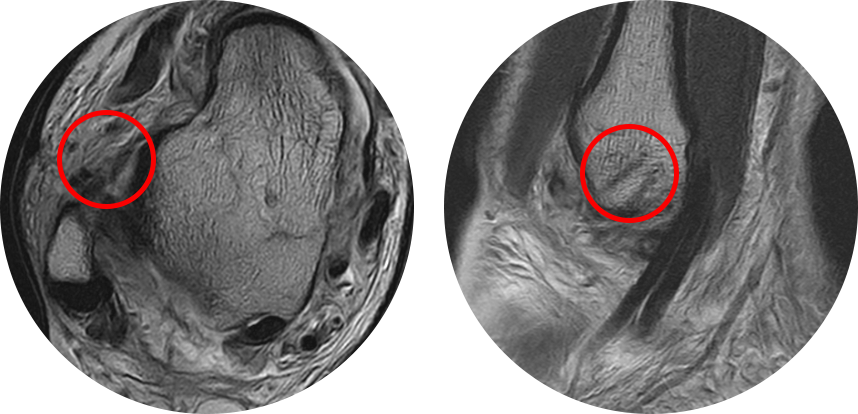

수술을 할 정도의 심한 인대 손상이 있는 경우 발목 연골 손상 등이 동반되는 경우가 쉬운데, MRI에서 놓치기 쉽고

경비인대 손상 중 일부는 관절경 하에서만 발견되는 경우도 흔하기 때문에 진단적인 목적으로 시행합니다.

수술 전 MRI 에서 전거비인대 및 종비인대의 완전 파열 소견을 보이며 관절내에 피가 고여 있는 모습이 관찰됩니다.

* 환자에게 받은 소중한 자료입니다.